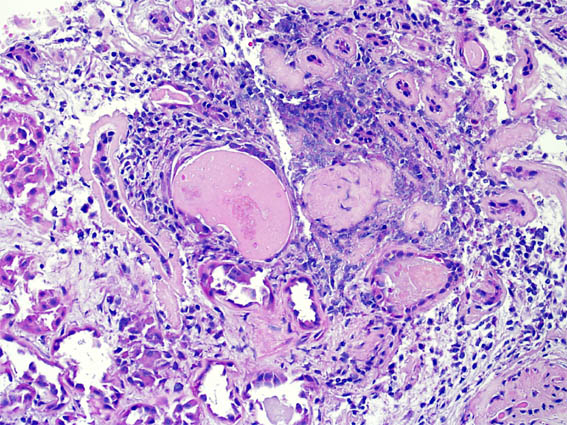

Figura 2.

H&E, X400.